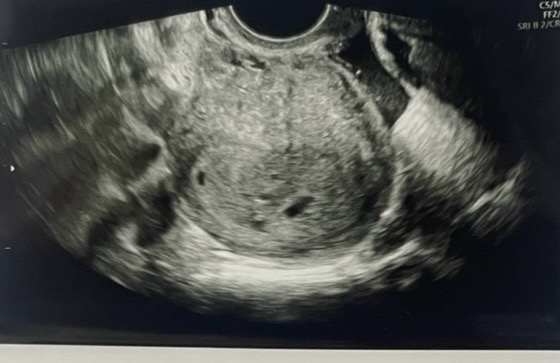

아가집 보고왔는데 집이 두개보여요✨

선생님이 쌍둥이 가능성이 보인다고 하는데 저 둥이엄마 될까요?ㅎㅎㅎ🤩 기쁜맘도 크지만 걱정도 앞서네요 ~~